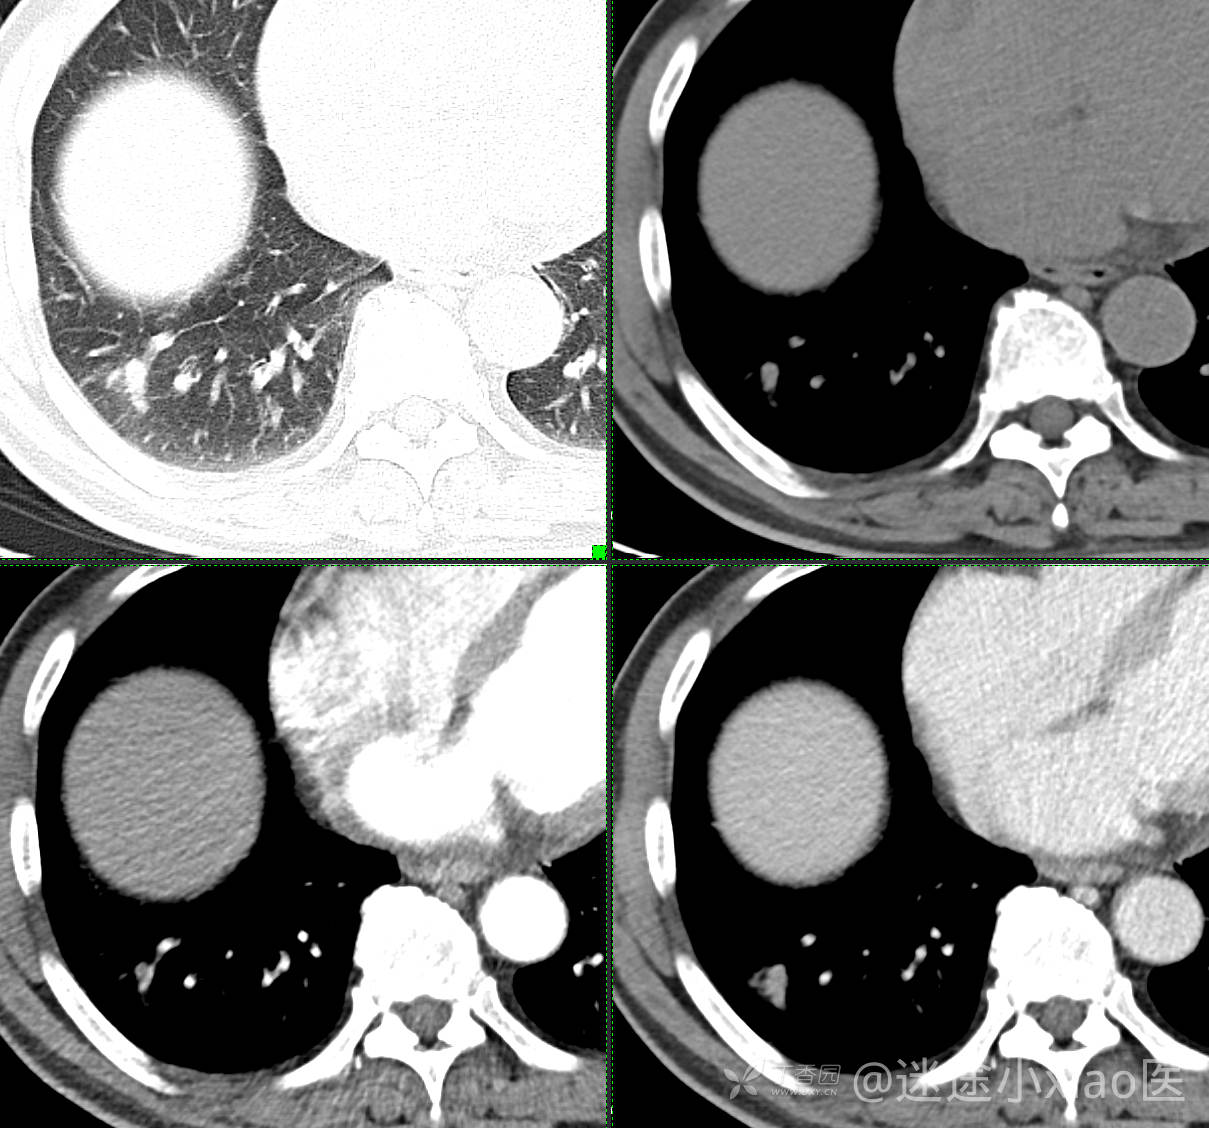

胸组50:老年男性,发现肺占位一天,(结果公布)

主诉: 发现右肺占位1天

现病史: 患者诉1日前在当地医院检查时胸部CT示;肺结节(具体不详),当时无胸闷气急。 无咳嗽咳痰,无胸痛,无恶心呕吐等。今为求进一步治疗,门诊拟“肺结节”收治入院。病来,患者神志清,精神可,胃纳睡眠可,二便无殊,体重无明显增减。